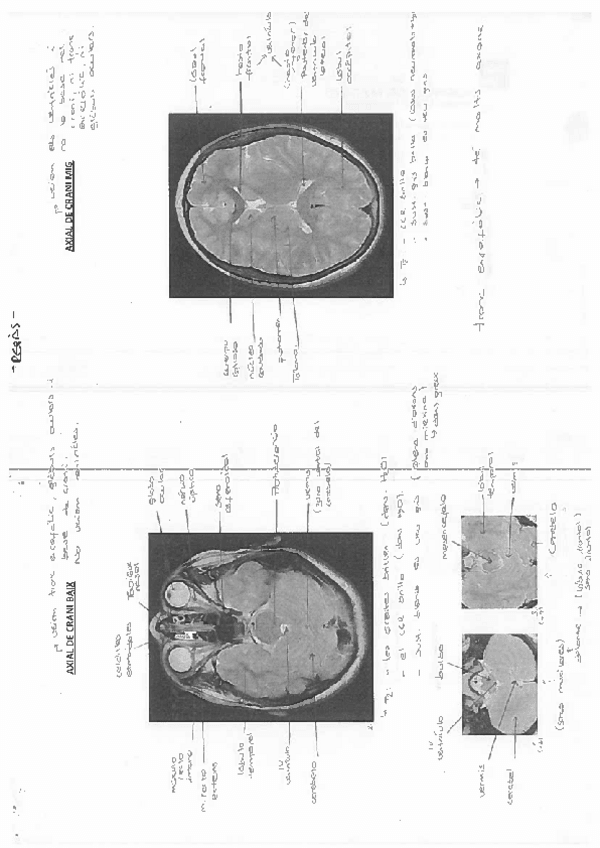

imagenes-2n-exam-rellenado.pdf

10 páginas